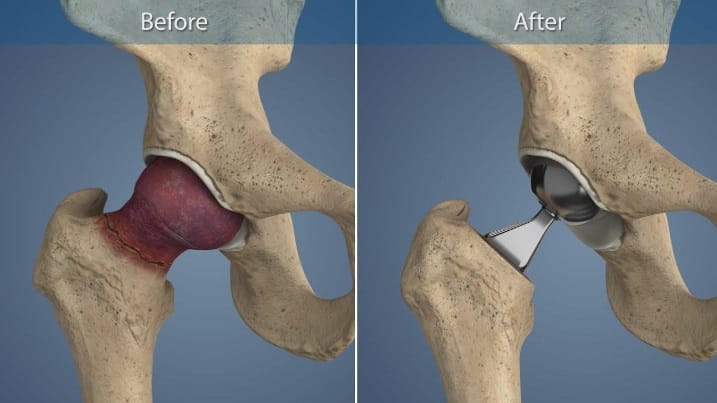

يتم خلال عملية تغيير مفصل الحوض استبدال وإزالة الجزء المتضرر من الورك أو عظم الفخذ بمفاصل وأجزاء صناعية؛ وذلك لعلاج الآلام الناتجة عن التهاب المفاصل والحالات التنكسية التي قد تصيب المفصل.

هذا الشق الجراحي سيتخلل طبقات الأنسجة، سامحًا للطبيب بإزالة الغضاريف والعظام المصابة والتالفة، مع التركيز على عدم المساس بما هو سليم منها، وبعد الانتهاء من هذه الخطوة يُزرع التجويف البديل الذي يحل محل الجزء العلوي من المفصل أعلى عظمة الفخذ، وفي النهاية يتم إدخال الجذع داخل عظام الفخذ العلوية، وتوضع فوقه الكرة البديلة التي تُحاكي حركة المفصل، ويتم في النهاية خياطة الجرح وتضميده جيدًا.